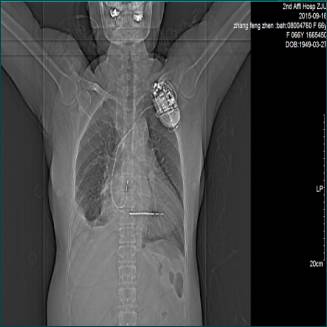

七.器官功能不全(2015.09.19)

肝脏功能不全:ALT:3946 U/L;

肾脏功能不全:Cr:168umol/L;

心脏功能不全:CTNI:0.401ng/ml ;Pro-BNP:16241 pg/ml

2015.09.19

2015.09.16

2015.09.18

2015.09.17

2015.08.03